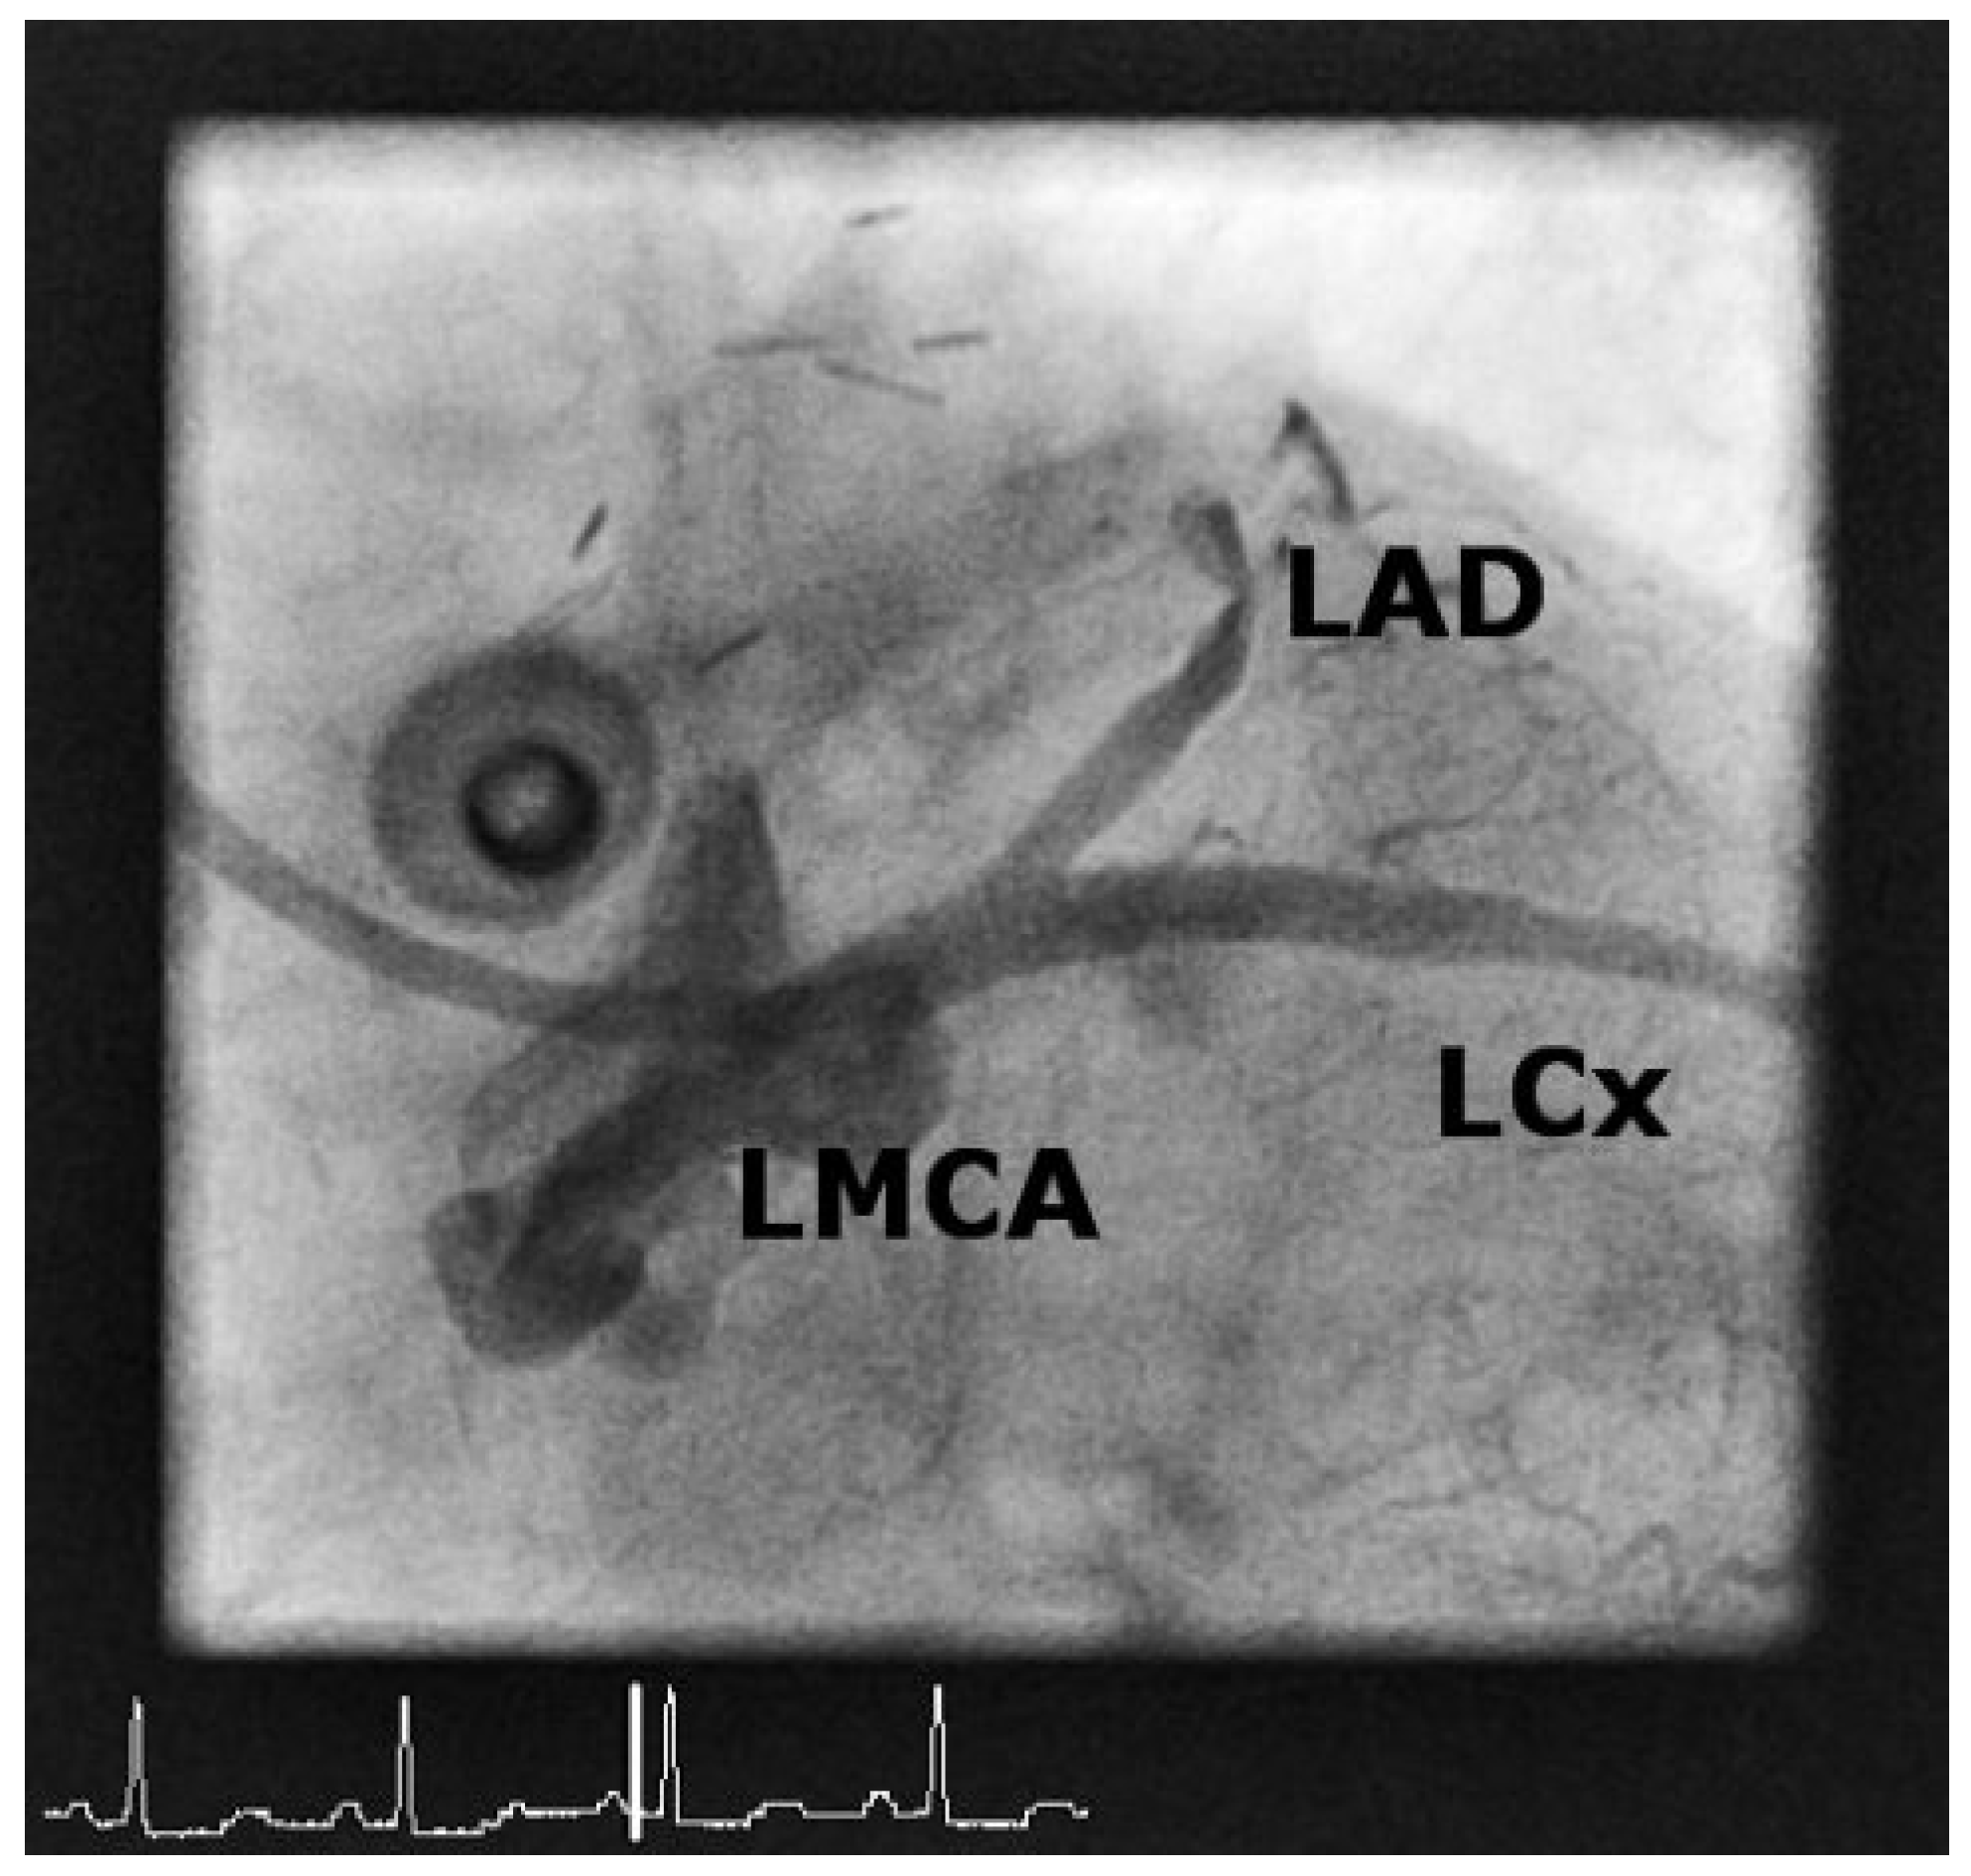

Case2